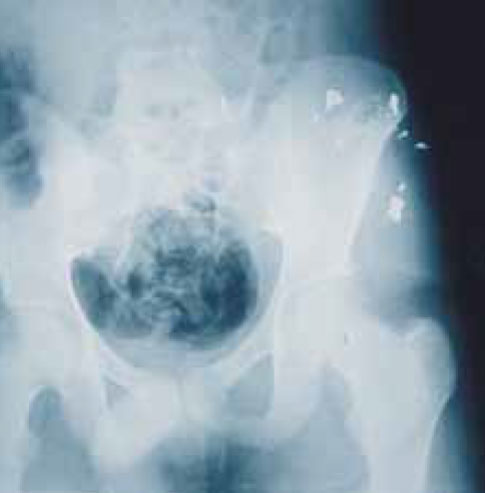

Рисунок 8. Разрушившаяся пуля в забрюшинном мышечном массиве